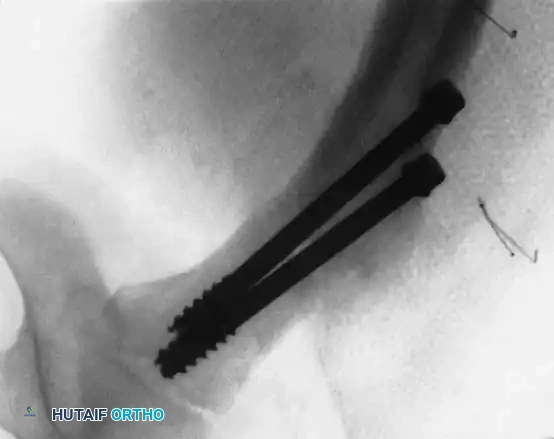

Management of Type II: Transcervical Fractures

Type II fractures are highly unstable. Even seemingly nondisplaced fractures will drift into coxa vara if treated with a spica cast alone.

- Fixation:

- Use two or three partially threaded cannulated screws (typically 4.5 mm or 6.5 mm depending on the child's size).

- Crucial Step: The pediatric femoral neck is extremely hard. You must overdrill the near cortex to achieve a lag effect and prevent fracture distraction.

- Stop the threads short of the physis to prevent growth arrest. Do not use adult triflanged nails, as the impaction force will distract the fracture or separate the physis.

Fig. 11: Transcervical fracture stabilized with cannulated screws stopping short of the capital femoral physis.

Fig. 12: Lateral fluoroscopic view confirming central placement of the screws within the femoral neck.